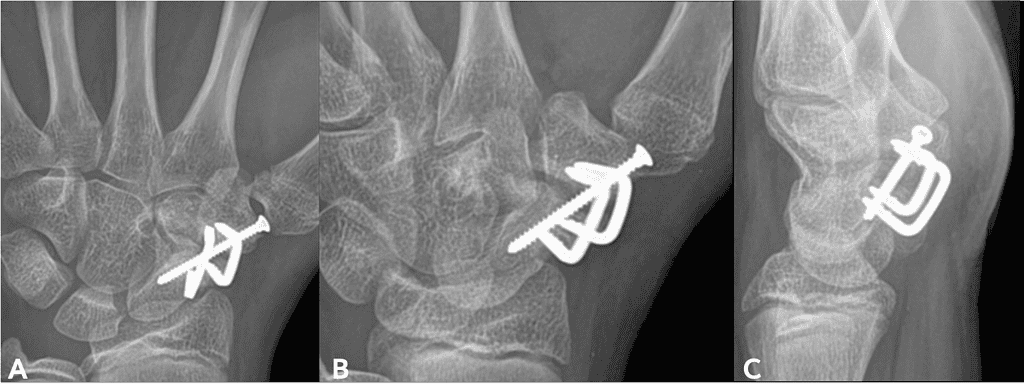

Figures 1-3 below descript the patient initial medical condition and subsequent surgical procedures prior to use of OSSIOfiber® implants

Screenshot 2026 01 20 At 2.47.37 Pm Ossio – Naturally Transformative Bone Healing

Figure 1: X-rays taken August 2022 at initial presentation; AP [A], Oblique [B] and Lateral [C]

Figure 3: Second surgery post-operative X-rays; AP [A], Oblique [B], and Lateral [C]